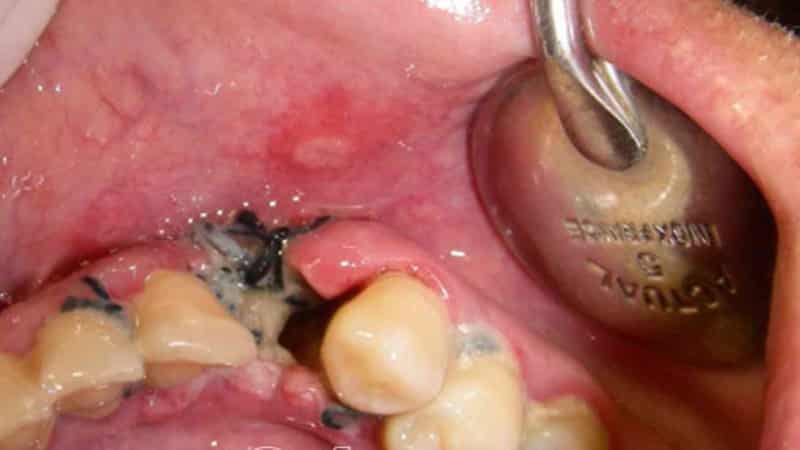

Отечность щеки после лечения

Часто после стоматологической процедуры по лечению зуба у пациента наблюдается значительное опухание щеки. Учитывая, что удаление проблемного зуба подразумевает вмешательство, которое может повредить десну, появление отека вполне объяснимо. Обычно такая отечность проходит в течение нескольких дней.

Физиологический отек, как правило, не вызывает болевых ощущений, имеет небольшие размеры и не требует хирургического вмешательства.

Однако в некоторых случаях речь идет о воспалительном процессе, который развивается в области вмешательства. Это может произойти при сложном удалении зубов, когда процедура сопровождается серьезными повреждениями.

Иногда причиной воспаления становится недостаточная квалификация врача, который не соблюдал гигиенические нормы во время операции, а иногда и сами пациенты, которые не следуют рекомендациям специалистов.